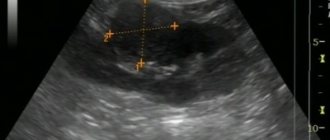

Ultrasound: Tumor of the right kidney